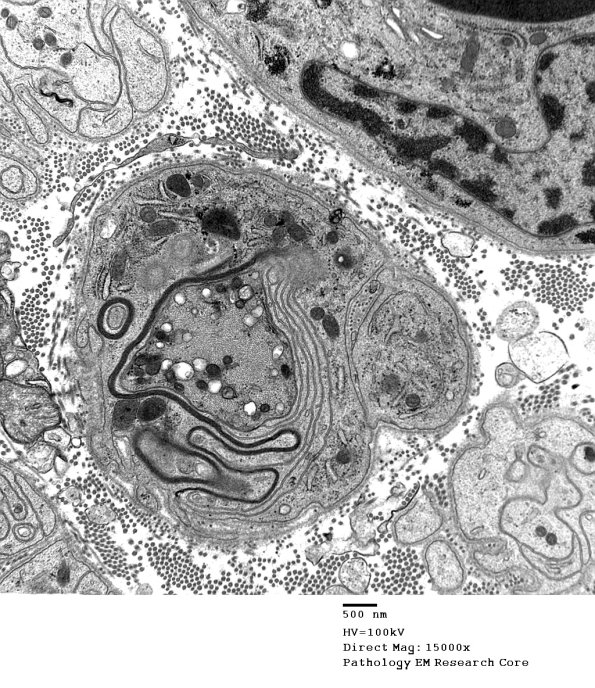

4C2,3 A complex non-compacted myelin sheath, evidence of remyelination. (electron micrographs)